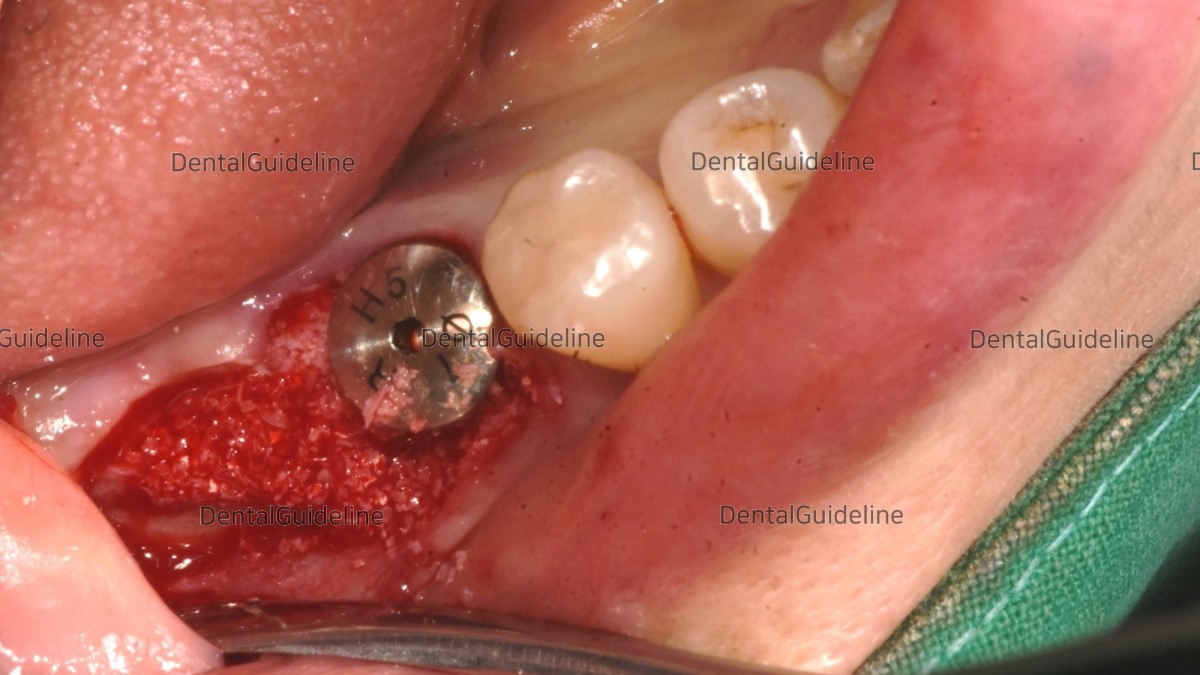

The choice of a healing abutment was engaged in the fixture of the 1st molar zone. And GBR was performed (xenograft).